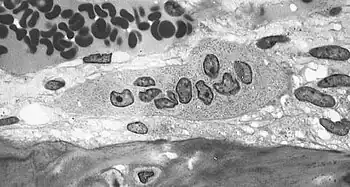

An osteoclast is a large multinucleated cell and human osteoclasts on bone typically have four nuclei[5] and are 150–200 µm in diameter. When osteoclast-inducing cytokines are used to convert macrophages to osteoclasts, very large cells that may reach 100 µm in diameter occur. These may have dozens of nuclei, and typically express major osteoclast proteins but have significant differences from cells in living bone because of the not-natural substrate.[6][7] The size of the multinucleated assembled osteoclast allows it to focus the ion transport, protein secretory and vesicular transport capabilities of many macrophages on a localized area of bone.

In bone, osteoclasts are found in pits in the bone surface which are called resorption bays, or Howship's lacunae. Osteoclasts are characterized by a cytoplasm with a homogeneous, "foamy" appearance. This appearance is due to a high concentration of vesicles and vacuoles. These vacuoles include lysosomes filled with acid phosphatase. This permits characterization of osteoclasts by their staining for high expression of tartrate resistant acid phosphatase (TRAP) and cathepsin K. Osteoclast rough endoplasmic reticulum is sparse, and the Golgi complex is extensive.[8][9][10]